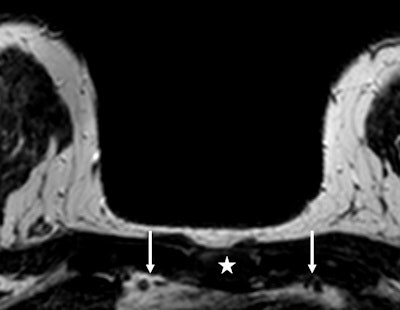

An example of the measurement of the cross-sectional area of the internal mammary vessels in a patient with a right-sided breast lesion of 1.9 cm. With sagittal reconstruction, the manubrium was marked (white star), which appears automatically in the transverse slices. On the transverse slice, using the marker the second intercostal space is recognized and the cross-sectional area of the internal mammary vessels (left and right arrows) can be measured. In this patient, the right internal mammary artery measured 5.21 mm2, compared with the left internal mammary artery of 4.12 mm2. Histopathology showed an invasive ductal carcinoma. Image courtesy of Dr. Robert-Jan Schipper.However, measurement of the internal mammary vessels has its shortcomings. "First of all, it is not possible in patients who have undergone a coronary artery bypass graft," Schipper and colleagues wrote. "After unilateral mastectomy, it is also not possible to make a reliable left-right comparison of the internal mammary vessels. It is unclear whether tissue sampling in the breast influences the cross-sectional area of the internal mammary vessels because of an inflammation reaction after sampling."